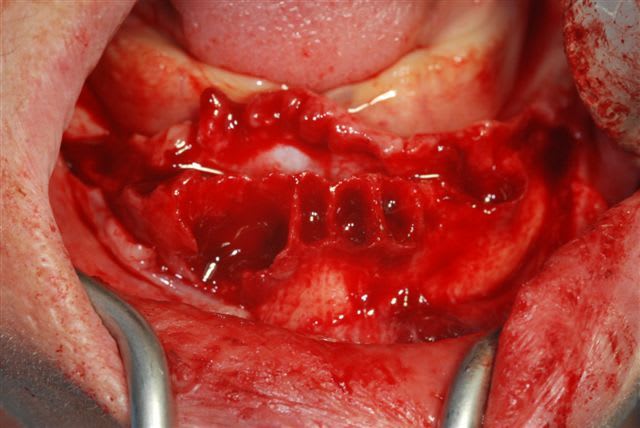

un petit cas clinique de cet après midi:

la pano post op

j'avais prévu de faire une MCI mais le manque de stabilité primaire des 2 implants côté droit m'en a dissuadé.

membrane biomend extend stabilisée par 2 petites vis de 4 mm de long de chez esasy implant. Os autogène et un peu de bio-os mélangé pour combler le defect.

Petite question : pourquoi ne pas avoir couvert le defaut crestal entre l'implant R1 et R2, est ce parce que tu voulais placer l'implant provisoire ?

"pourquoi ne pas avoir couvert le defaut crestal entre l'implant R1 et R2, est ce parce que tu voulais placer l'implant provisoire ? "

en fait avant de placer l'implant provisoire et de suturer, j'ai mis en place une membrane biogide par dessus cette zone pour bien la recouvrir. L'implant provisoire de ce côté traverse la membrane biogide dans laquelle j'avais ménagé (pour le fun)un petit trou avec la pince à perforer les digues. malheureusement je n'ai pas pu prendre l'ensemble des photos que j'aurais souhaité.